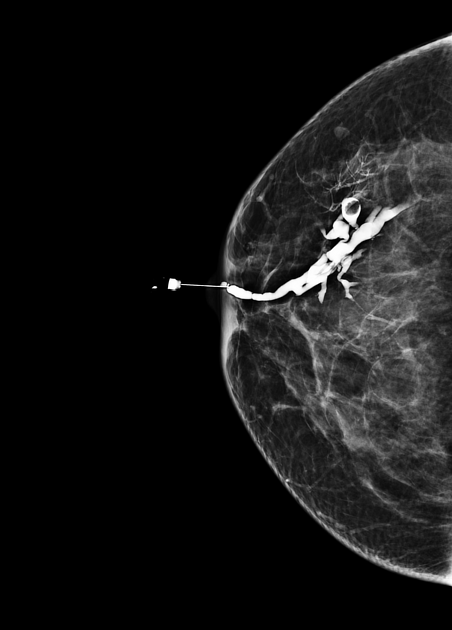

Galactography or ductography (or galactogram, ductogram) is a medical diagnostic procedure for viewing the milk ducts. The procedure involves the radiography of the ducts after injection of a radiopaque substance into the duct system through the nipple. The procedure is used for investigating the pathology of nipple discharge.

Galactography is capable of detecting smaller abnormalities than mammograms, MRI or ultrasound tests. With galactography, a larger part of the ductal system can be visualized than with the endoscopic investigation of a duct (called galactoscopy or ductoscopy).